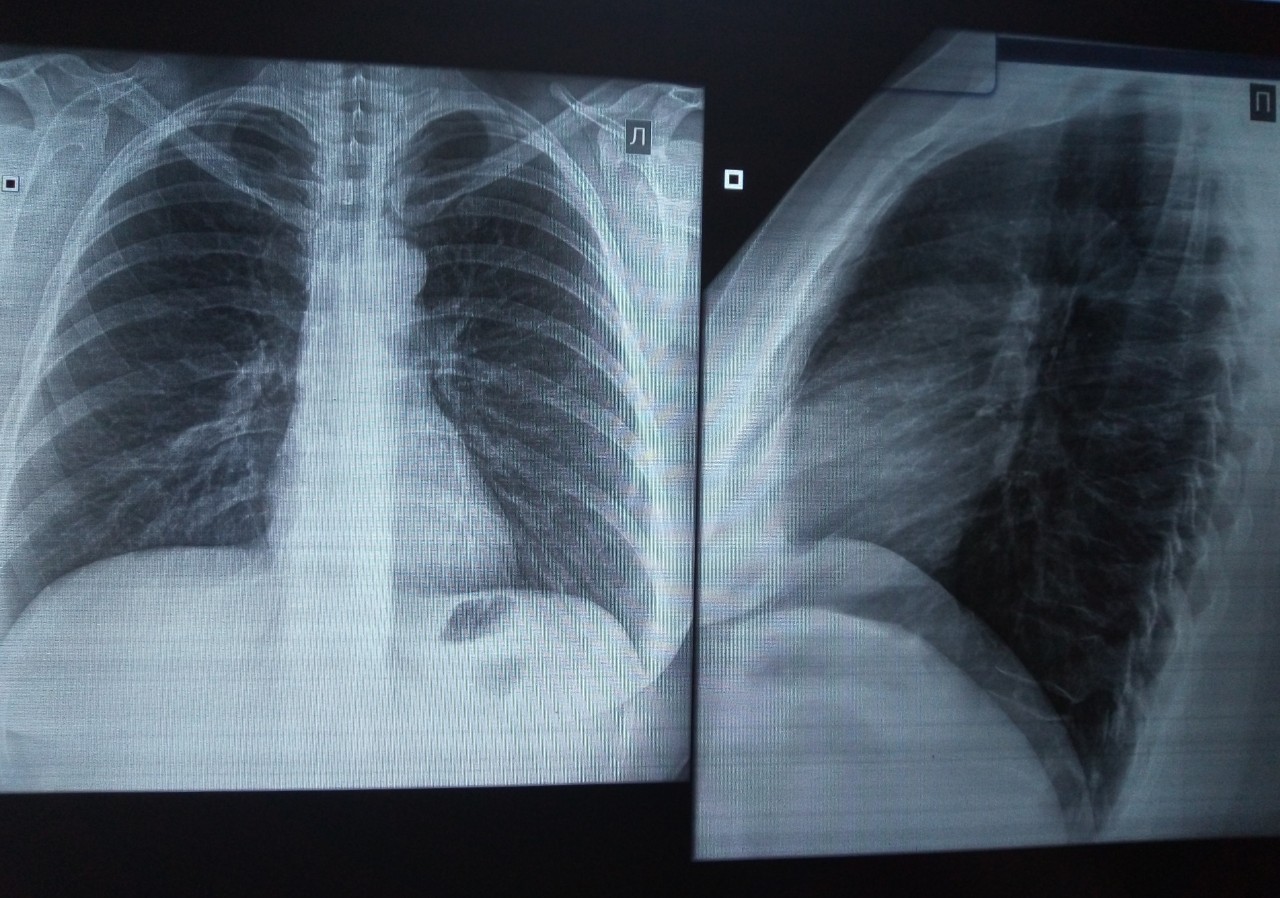

Нормальная рентгенограмма легких: что нужно знать

Раздел: Мудрость в объективе